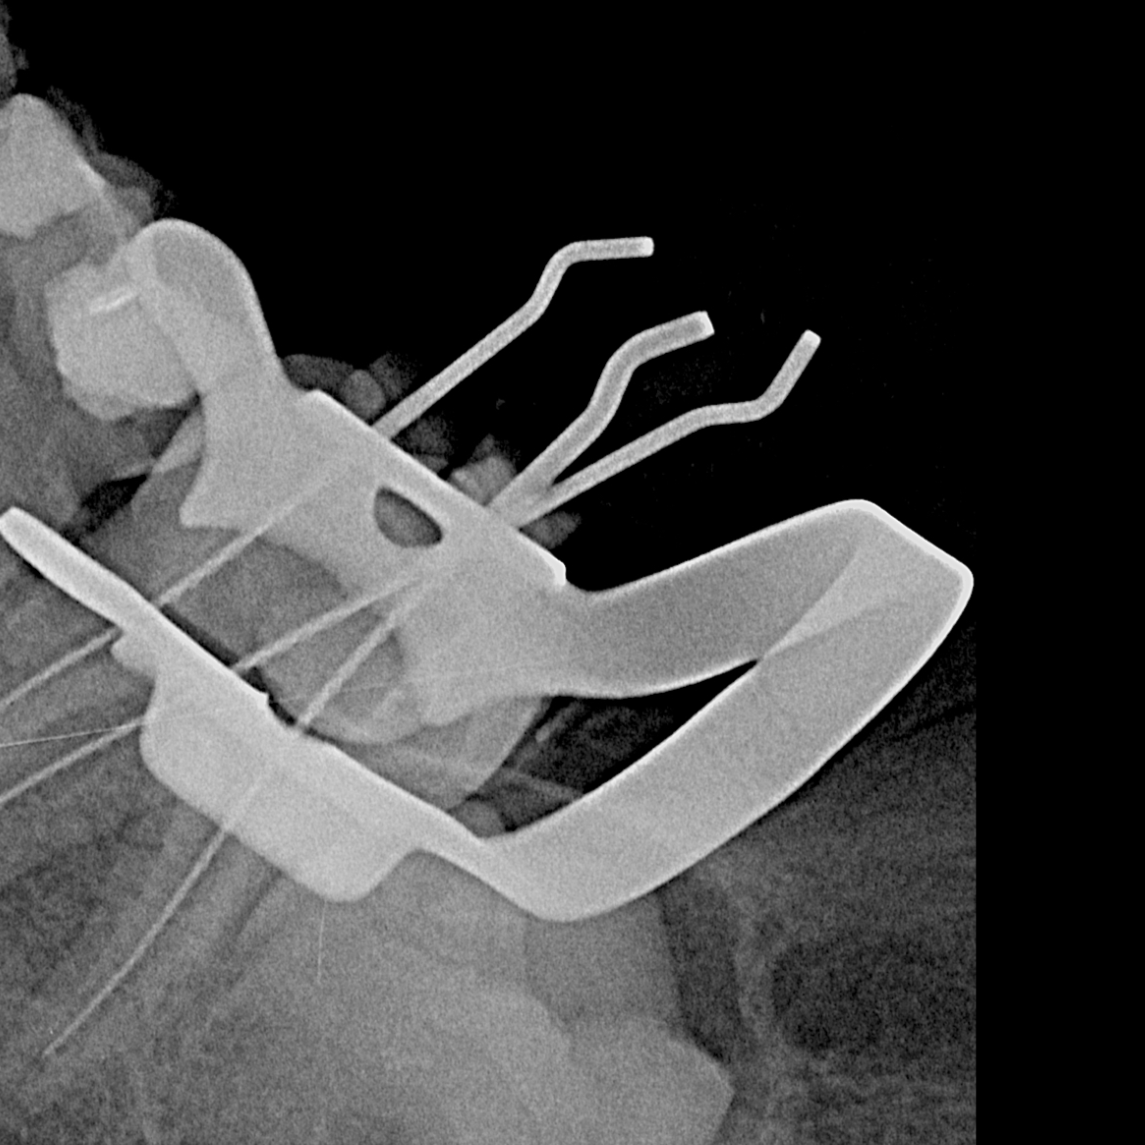

La endodoncia posterior es un tratamiento odontológico que se realiza en los dientes posteriores...